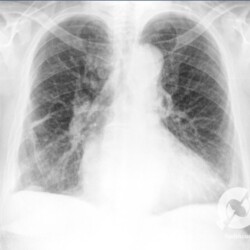

Aumento do volume cardíaco, inversão da circulação pulmonar, lesões intersticiais reticulares e obliteração dos seios costofrênicos.